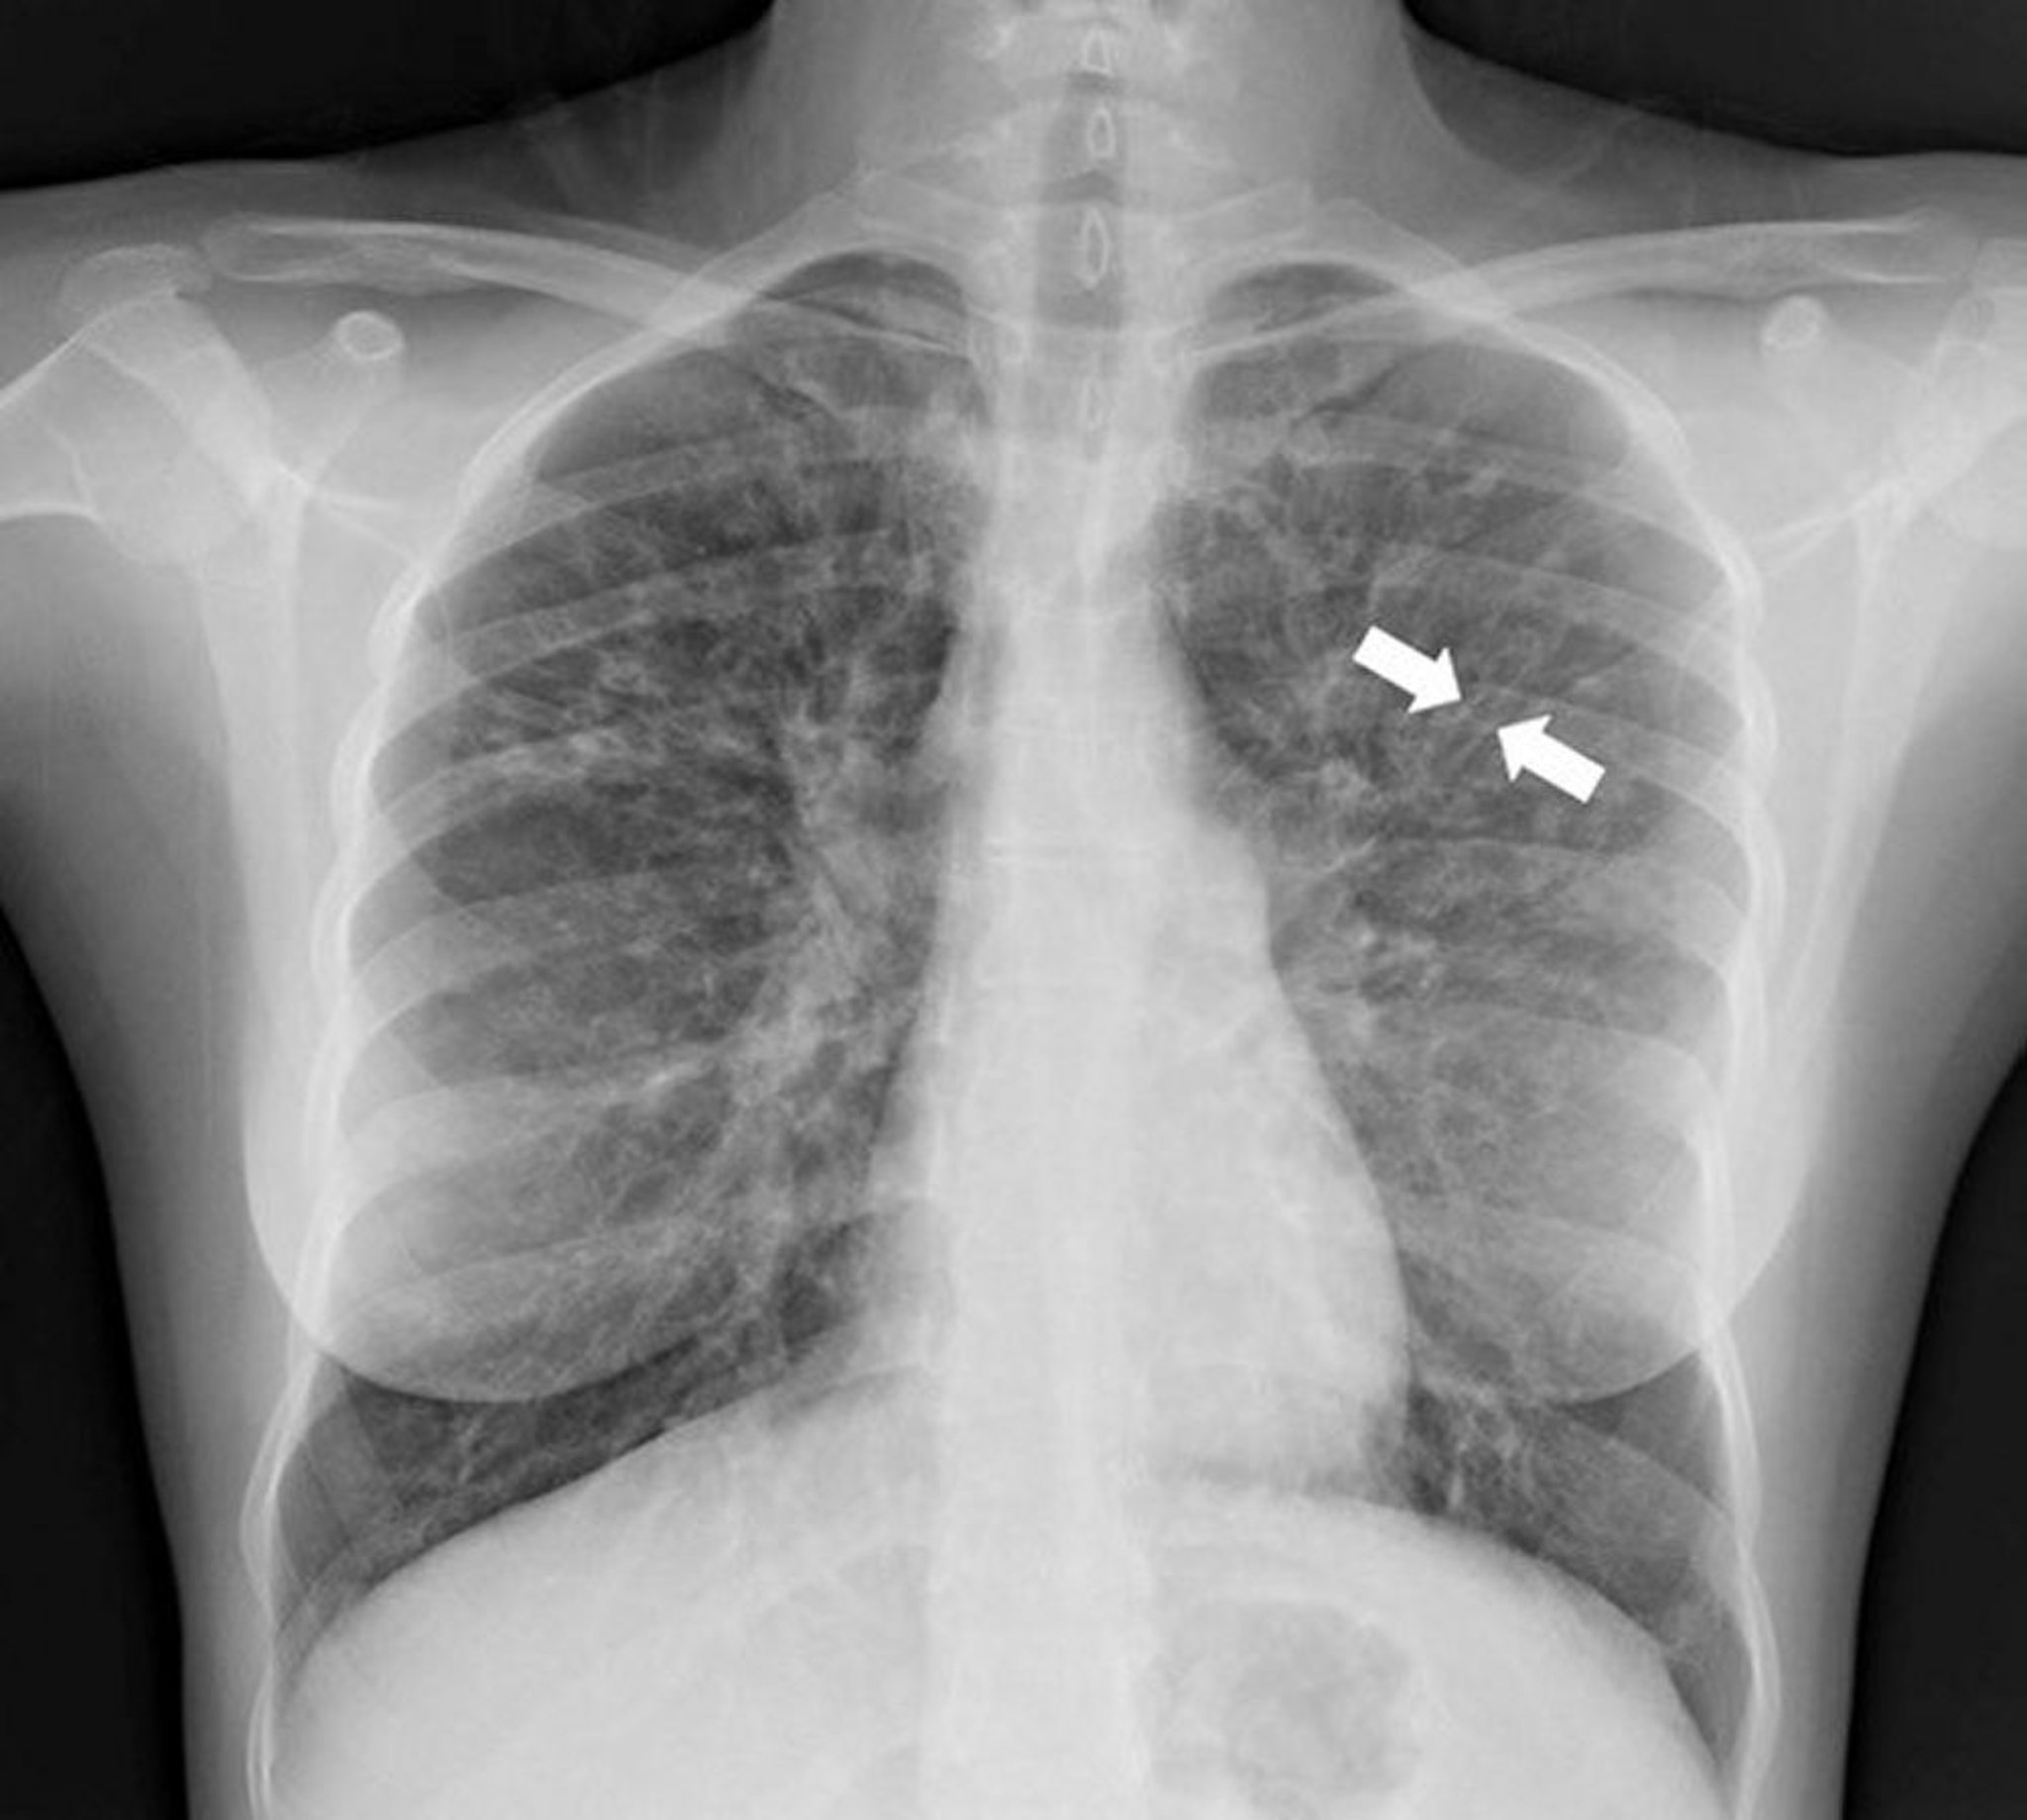

A radiografia de tórax isolada pode às vezes ser diagnóstica. Os achados radiográficos sugestivos de bronquiectasia envolvem um espessamento das paredes e/ou dilatação das vias respiratórias; os achados típicos incluem densidades peri-hilares lineares mal definidas com indistinção das artérias pulmonares centrais, anéis indistintos em razão do espessamento das vias respiratórias vistos transversalmente (paralelo ao feixe de radiografia), e "trilhos de trem" (ou sinal do trilho de trem) causados por vias respiratórias espessadas e dilatadas perpendiculares ao feixe de radiografia. As vias respiratórias dilatadas preenchidas por tampões mucosos também podem causar opacidades tubulares alongadas dispersas.

Os padrões radiográficos podem diferir com base na doença subjacente; a bronquiectasia decorrente da fibrose cística se desenvolve predominantemente nos lobos superiores, enquanto a bronquiectasia causada pela obstrução endobrônquica provoca mais anormalidades focais na radiografia.